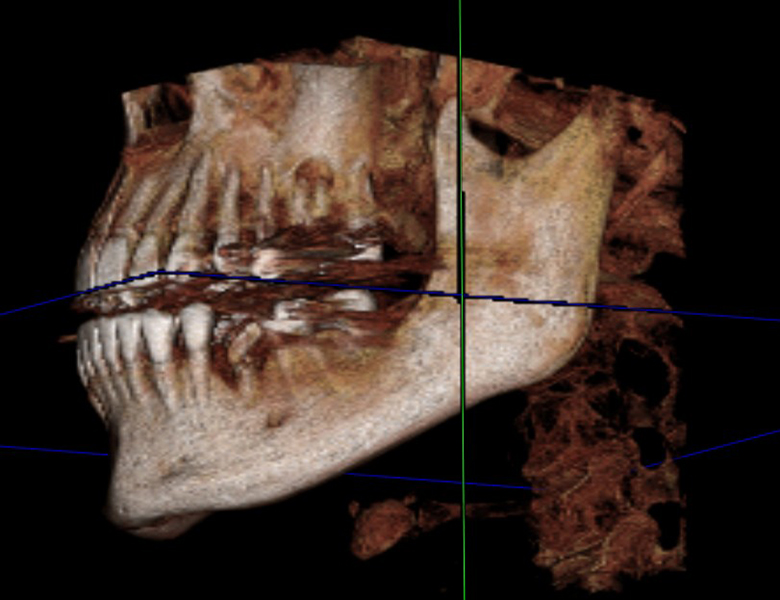

インプラント埋入部位の骨量骨質の確認

親知らずの抜歯時の神経との位置確認

根管治療の精密診断と根の先の病変の確認

歯周病の進行度の確認

矯正治療において歯の根の方向や顎の骨との関係を立体的に把握

従来の平面的なレントゲンでは見えなかった、隠れた病変や複雑な構造まで正確に把握できるのが、当院が導入している歯科用CTです。

むし歯や歯周病、親知らず、根管治療、矯正治療、インプラント治療など、さまざまな歯科治療の診断・精度向上のために用いられるのがこの歯科用CTスキャンです。